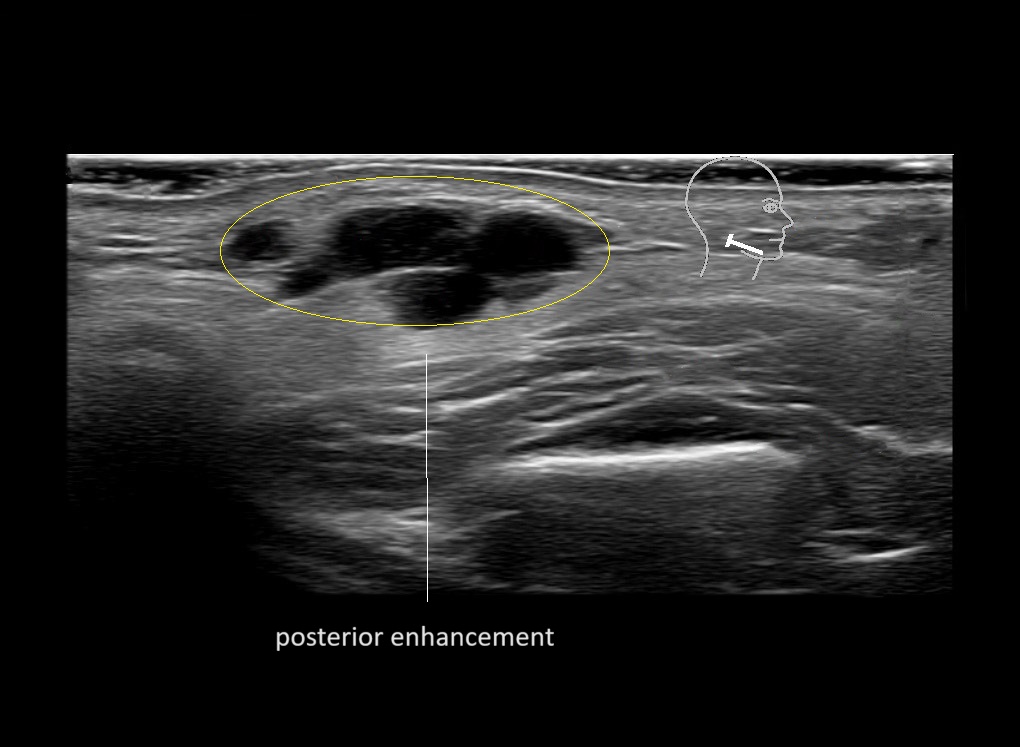

Filler injections in the parotid gland may go unnoticed, however, inflammatory reactions and abscesses may occur. Hypervascularity can be seen with color doppler. Filler deposits are supposed to be injected into the superficial fatty layer . The space to inject into this layer may be limited. Routinely we measure a width of 2-4 millimeters with sometimes subcutaneous layers being less than one millimeter thick.

Study the first image to recognize the different layers. If you are sure about the layers, swipe to the second image to view the answer (if applicable).